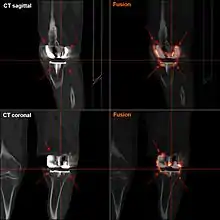

Components and zones

Standardized zones around the components are used for specifying, for example, signs of loosening on radiographic follow-up. There are various classification systems for specifying such zones,[45][46] including by KS (Knee Society) zones published in 2015.[44]

Main components of a knee prosthesis.

KS zones, anteroposterior (AP) view.[44]

Specific KS zones are as follows, with * meaning that the zone can be specified as "A" (anterior), "P" (posterior), "M" (medial) or "L" (lateral):[44]

- Femoral component (lateral view)

- Zone 1 and 2: Anterior and posterior flange, respectively.

- Zone 3: Central box/distal fixation region, where "A" and "P" designate the respective chamfers if visible*

- Zone 4: Stem extension*

- Zone 5: Stem

- Tibial component:

- Zone 1: Anterior on lateral view, medial on anteroposterior (AP) view.

- Zone 2: Posterior on lateral view, lateral on AP view.

- Zone 3: Central keel/stem/peg fixation region*

- Zone 5: Inferior aspect of keel or stem